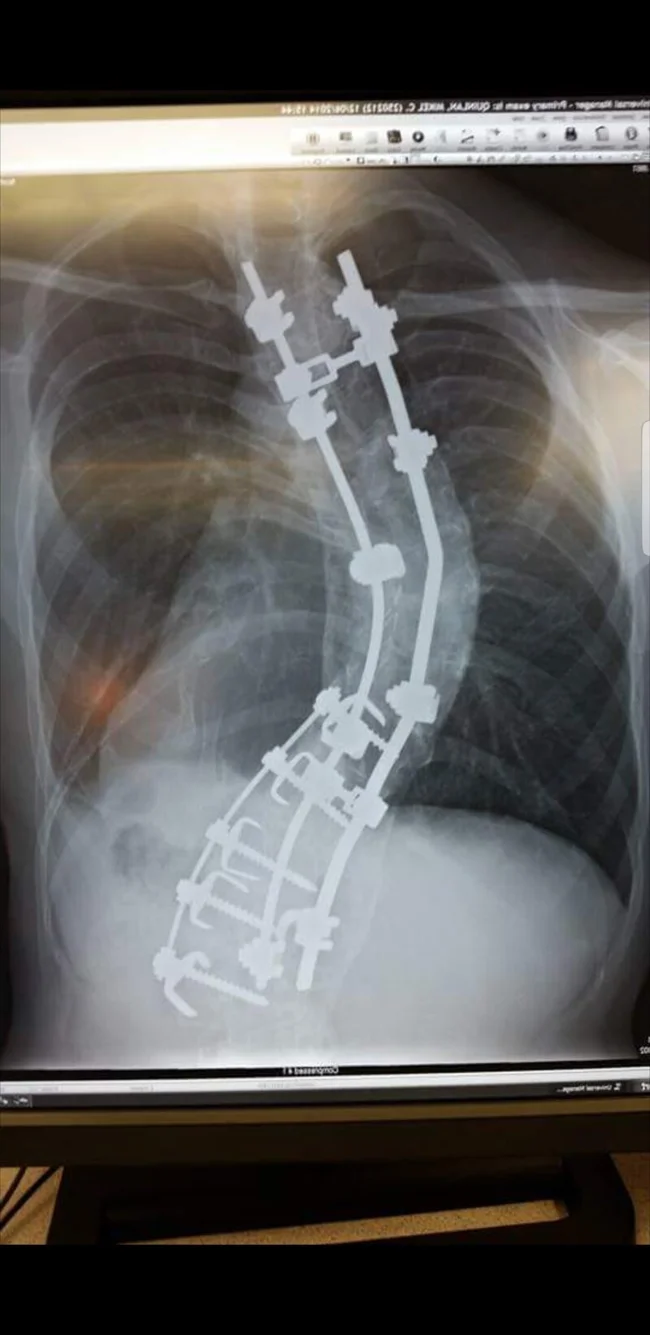

Позвоночник с высокой степенью сколиоза после операции по выпрямлению